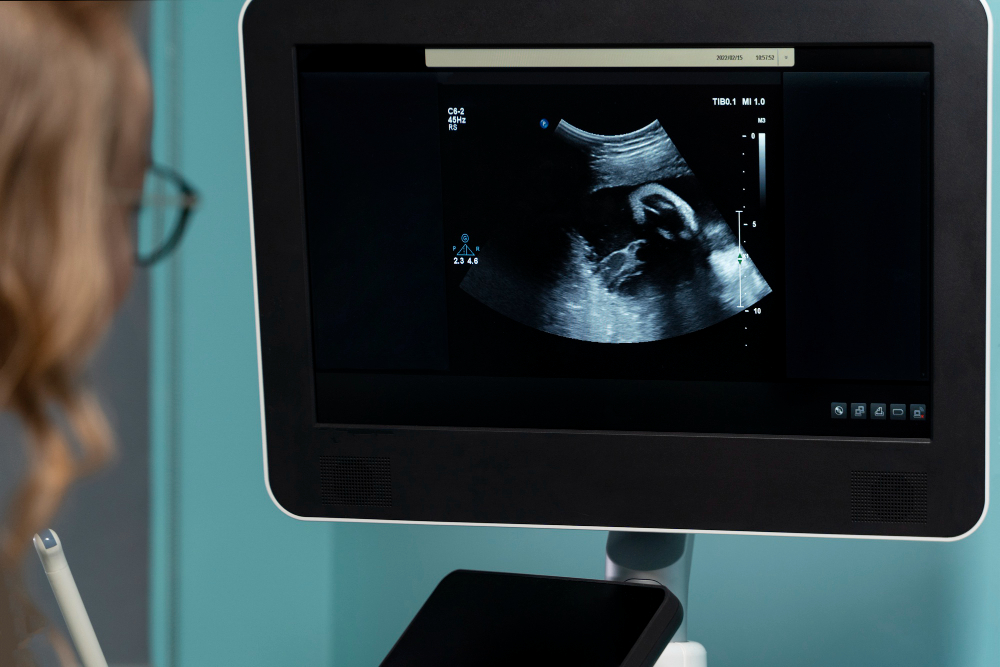

Doctors use several methods to diagnose oligohydramnios. Usually, they start with a physical exam and ask about your symptoms. Next, they may use an ultrasound to measure the amount of amniotic fluid. The most common test is the Amniotic Fluid Index (AFI). If the AFI is low, it suggests oligohydramnios. Sometimes, doctors use another test called the Maximum Vertical Pocket (MVP) measurement. In addition, your doctor may check your baby’s growth and heartbeat. Early diagnosis helps guide the best treatment for you and your baby.